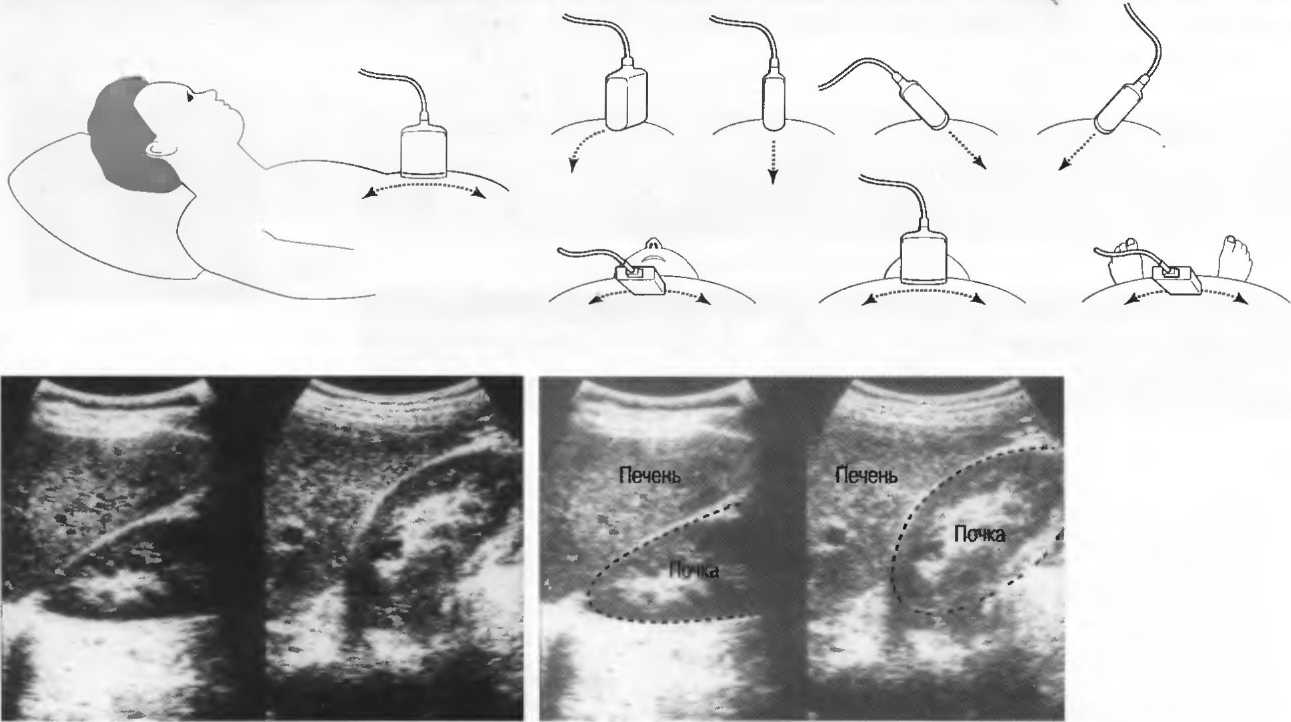

Рис.22. Изображения одной и той же структуры тела из разных положений и с различным углом наклона датчика. Слева: хорошо визуализируется только верхний полюс почки. Справа: изображение верхнего полюса почки смазано, но остальная часть визуализируется хорошо.

4. У здоровых обследуемых паренхима печени должна быть немного более эхогенна. чем кора рядом расположенной почки (рис. 26).

Рис.26. Продольный срез через печень и правую почку: нормальная паренхима печени более эхогенна, чем паренхима нормальной почки. Это еще один способ проверки качества изображения.